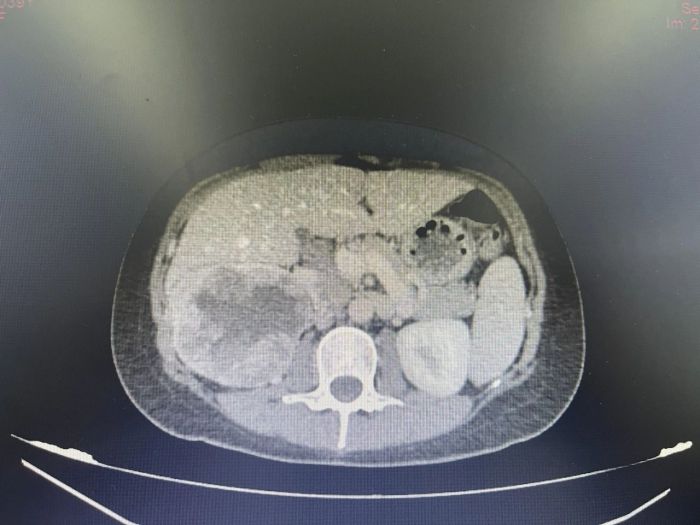

申智勇博士门诊详细了解了陈女士的病情后,结合科室此前多次成功案例,决定采用术前新辅助靶免治疗后再进行手术的方法,遂安排患者入院。后经过进一步相关检查,提示右肾占位,肾恶性肿瘤可能性大,局部肾周粘连严重,肝下缘与肿瘤无明显界限,肾门淋巴结肿大并融合,与右肾静脉、右肾动脉分界不清,进一步行“经皮肾肿瘤穿刺活检术”后,病理结果回示:符合肾透明细胞肾细胞癌。

靶向联合免疫治疗前